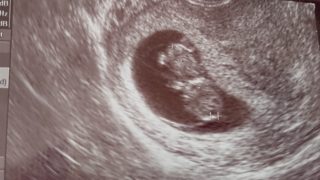

おそらさんが生まれるまで。(妊娠初期から胎児水腫が分かるまで)#1

おそらさんが生まれるまで。#1